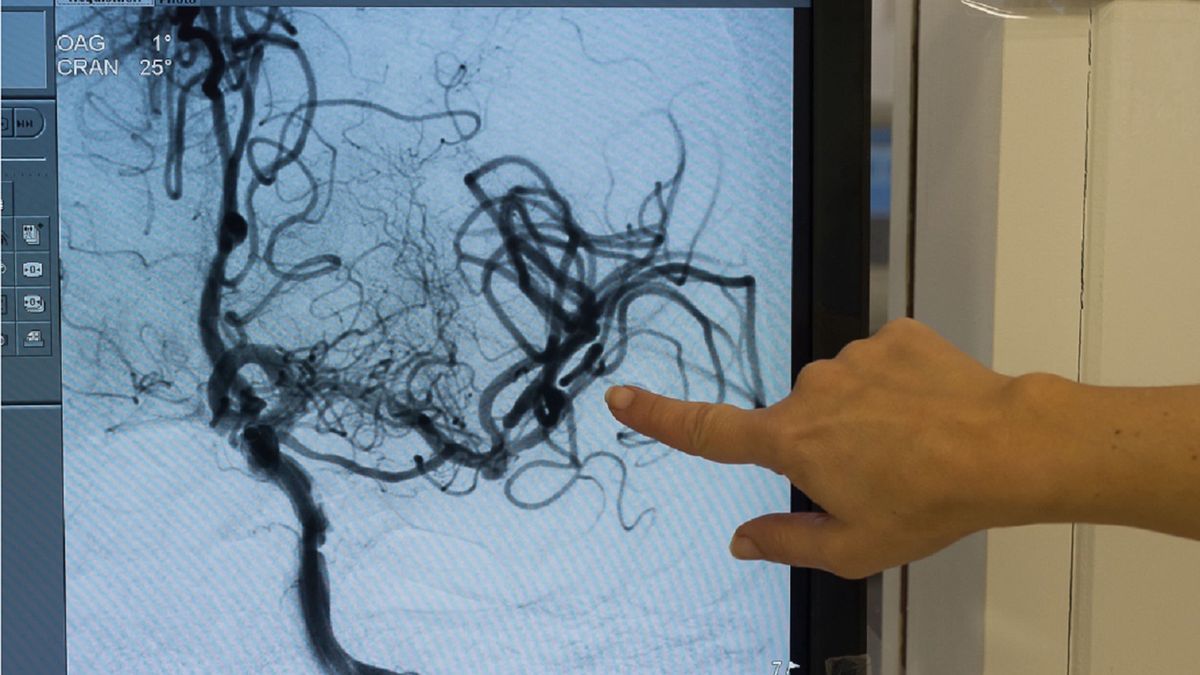

- Między sobą mówimy już o udarach covidowych. Koledzy radiolodzy, którzy oglądają obrazy głowy pacjentów po udarach z COVID, mówią, że obraz jest zupełnie nietypowy, te ogniska są rozsiane, co wskazuje na rozsianą angiopatię (choroba małych naczyń mózgowych - przyp. red.). U pacjentów zakażonych koronawirusem na pewno dochodzi do uszkodzenia śródbłonka. Z badań autopsyjnych u zmarłych zakażonych koronawirusem wiemy, że stwierdzono u nich nadkrzepliwość i uszkodzenie tętnic. To mogą być jedne z czynników, które przyczyniają się do rozwoju udarów u tych pacjentów - tłumaczy dr Kobayashi.